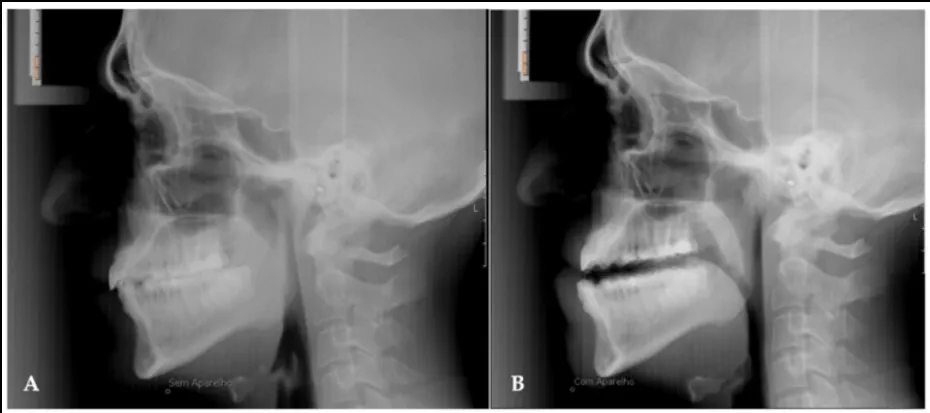

Bei mittelschweren und schweren Formen des SAS kann eine Operation in Frage kommen. Die international am häufigsten durchgeführte Operation zur Behandlung des Schlafapnoe-Syndroms ist eine Vorverlagerung des Ober- und Unterkiefers (Maxillomandibuläres Advancement). Es gibt dabei zwei Arten der Vorverlagerung. Die gewöhnliche Vorverlagerung behebt nach den Erfahrungen von Wissenschaftlern etwa 40% die Schlafapnoe. Die erweiterte Operation mit noch stärkerer Erweiterung der Atemwege kann eine Heilungsquote von bis zu 80% erreichen. (1)(2)(3)

Außerdem gibt es noch die Operationsvarianten bei denen die Nase verändert, die Mandeln entfernt (Tonsillektomie), der weichen Gaumen oder der Zungengrund verkleinert. Experten sagen hierzu, dass sich die Schlafsituation zwar positiv ändert, aber das Schlafapnoe-Syndrom nicht deutlich verbessert wird. (4) Seit kurzer Zeit schlagen Mediziner die kombinierte Atemwegs- und Adipositaschirurgie (CABS) bei fettleibigen Personen vor, um gleichzeitig Adipositas als auch SAS zu verbessern. (5)